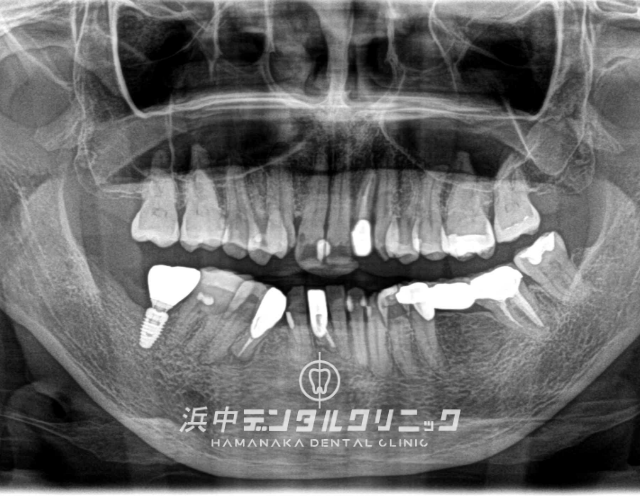

下顎両側7番が歯根破折で抜歯になり、インプラント治療して咬合機能を回復した症例(50代 男性)

BEFORE

AFTER

患者様の主訴

下の両方の奥歯が割れたので噛めるようにしたい。

診断結果

日常的に強い歯ぎしりをしてる患者様で下顎左右の7番目の歯が歯根破折をしてました。

治療内容

下顎左右両側の7番目の歯を抜歯後にインプラントを埋入して仮歯を経て最終上部構造(ジルコニアセラミック)をスクリュー固定しました。

治療後経過

インプラント治療終了後から約3年経過していますが全く問題なく経過良好です。

| 治療期間 | 約7ヶ月 |

|---|---|

| 治療にかかった費用 | インプラント体(フィスクチャー308,000円)×2本 +インプラント土台(アバットメント77,000円)×2本 +インプラント人工歯(上部構造ジルコニアセラミック165,000円)×2本 +静脈内鎮静麻酔77,000円+仮歯代22,000円×2本分 +サージカルステント55,000円 =合計1,276,000円 |

| リスク副作用 | インプラントは入れたら終わりではなく、きちんとメンテナンスしないと歯周病になることもあるので、定期的にクリーニングや噛み合わせの調整が必要です。 |